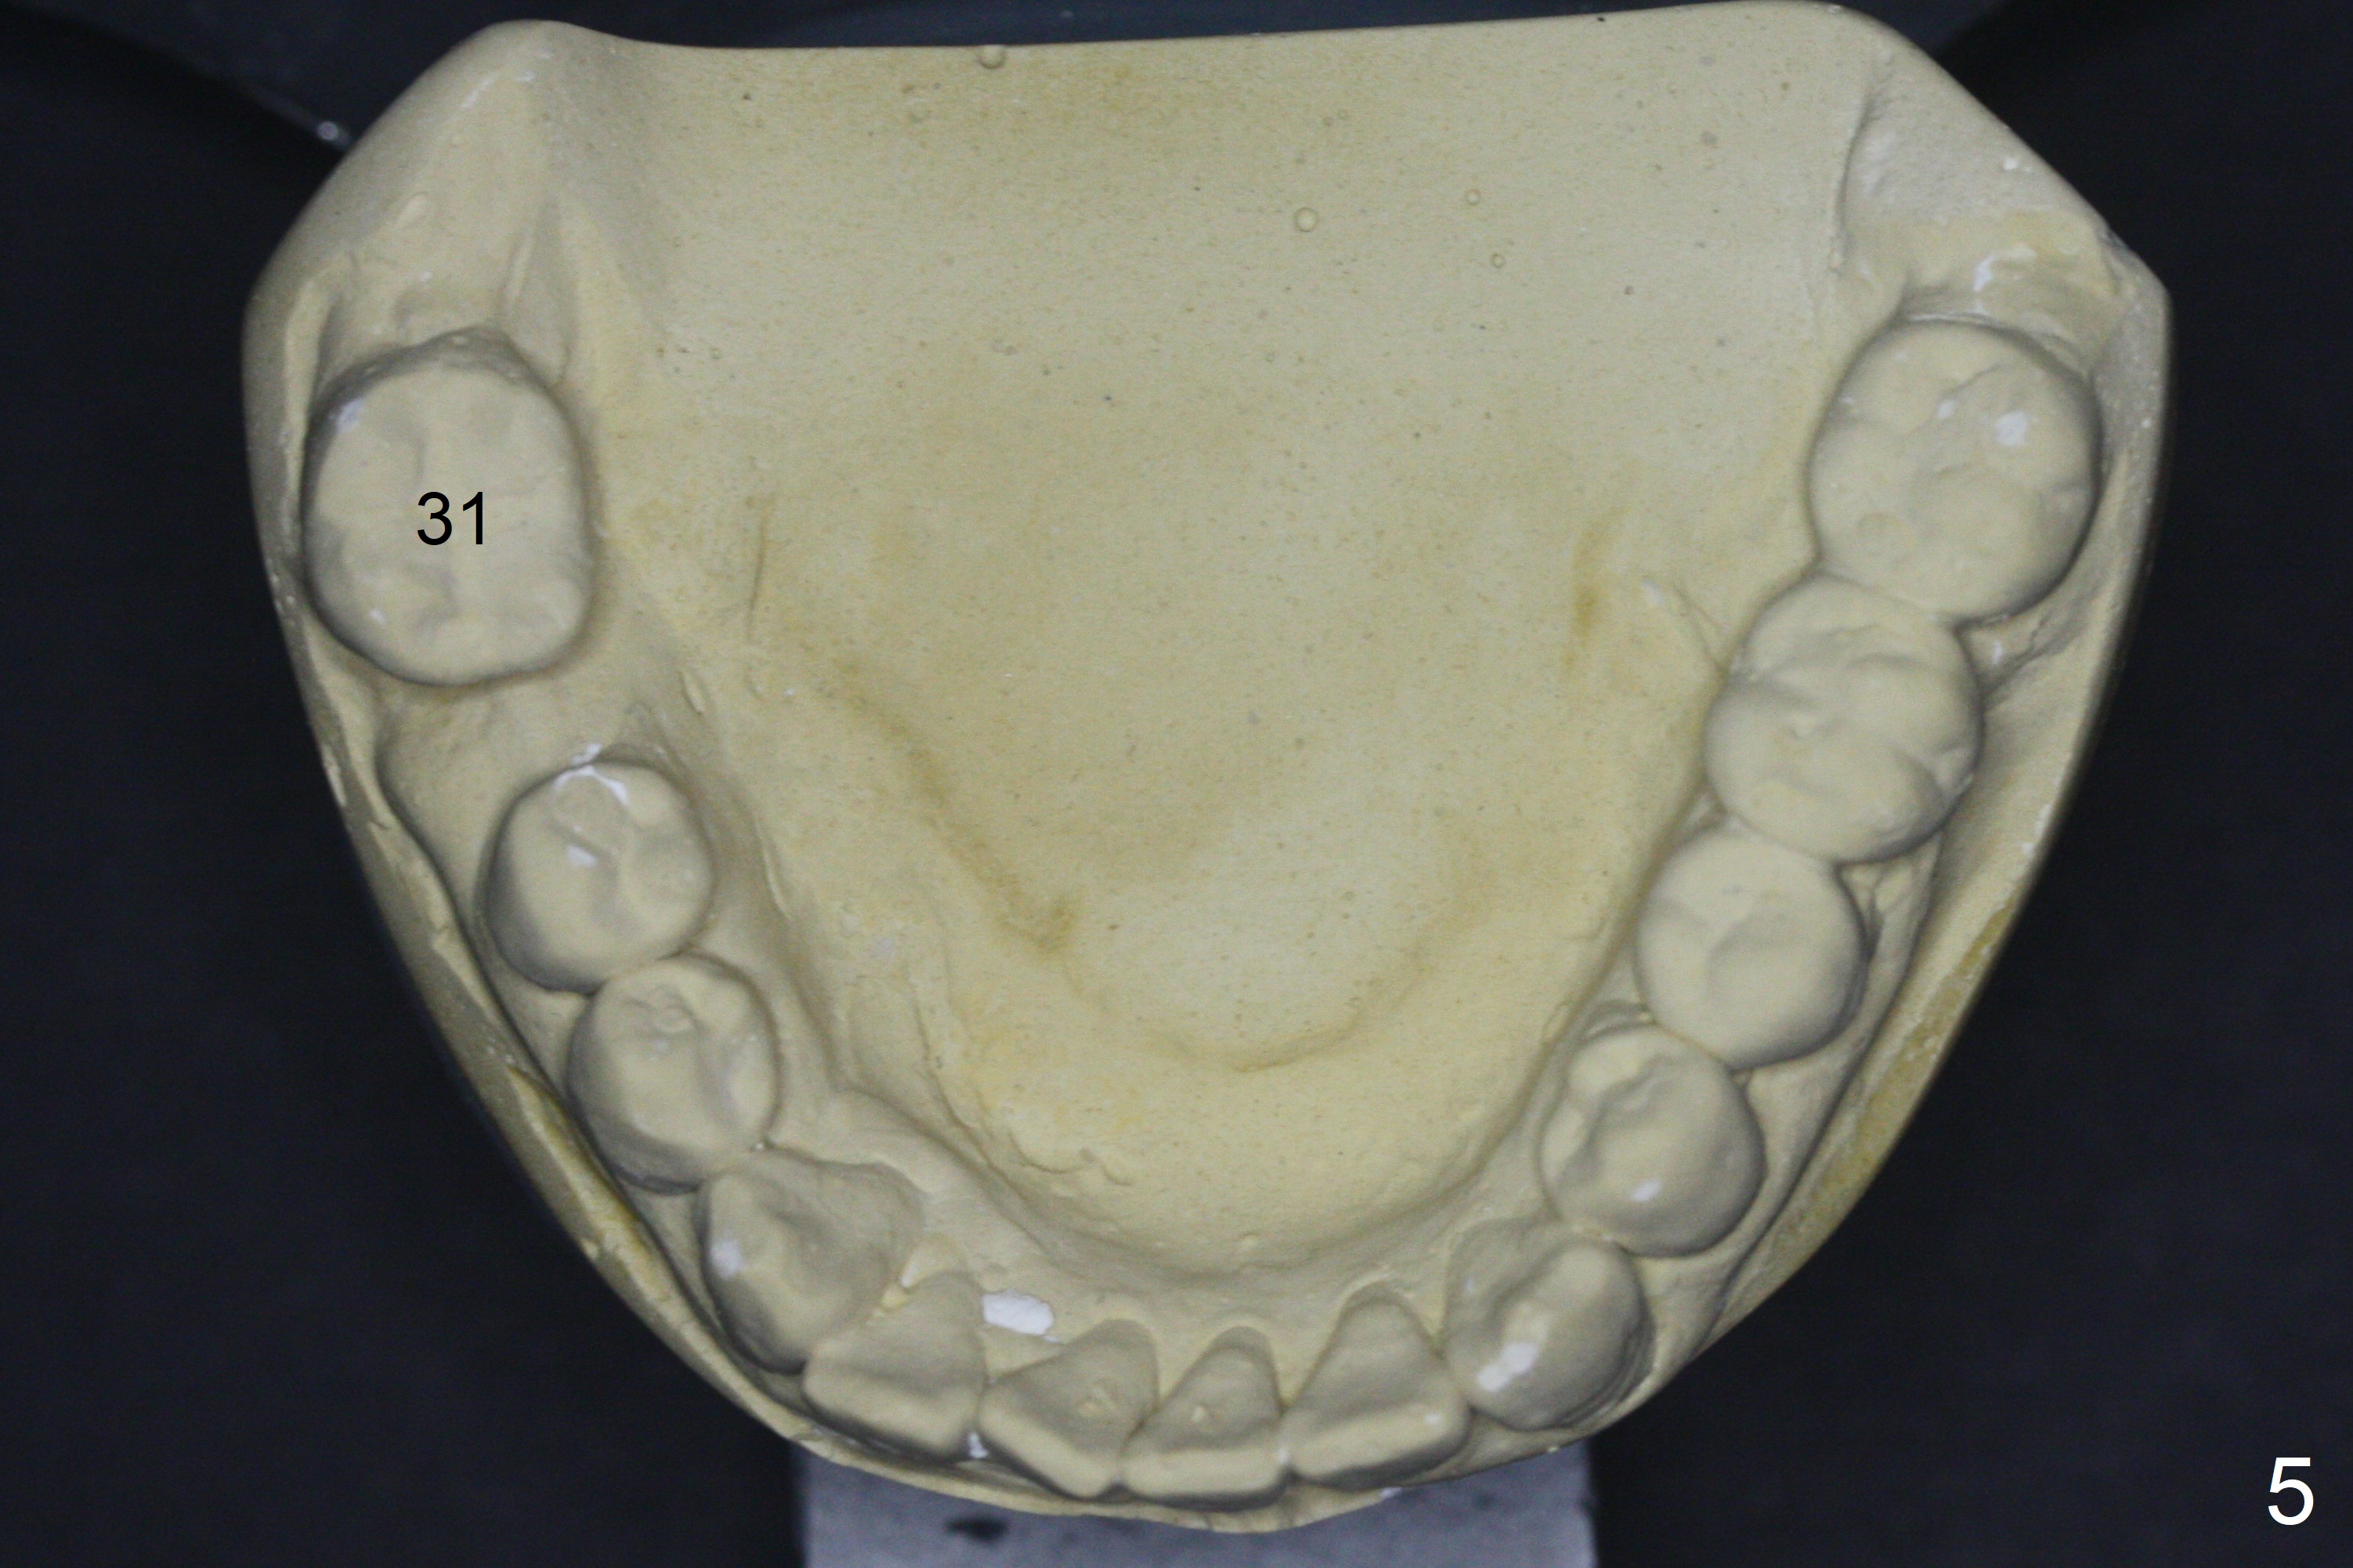

A 64-year-old man has discomfort with the lower left bridge and a loose tooth on the left (Fig.1). It appears that 4 implants are to be placed at #18,19,30 and 31. Since the tooth #4 and 13 are palatalized (Fig.2-4), the teeth #2 and 3 are mesialized (Fig.2 arrow). Besides, the ridge at #30 must be atrophic due to long termed edentulism. A small-diameter implant will be placed at #30 with premolar width (Fig.6-13), while the implant at #31 will be placed distal (arrow, as compared to Fig.2). To establish harmonious occlusion at provisional and final stages, the palatal slope of the mesiopalatal cusp of the tooth #2 will be adjusted (Fig.10).